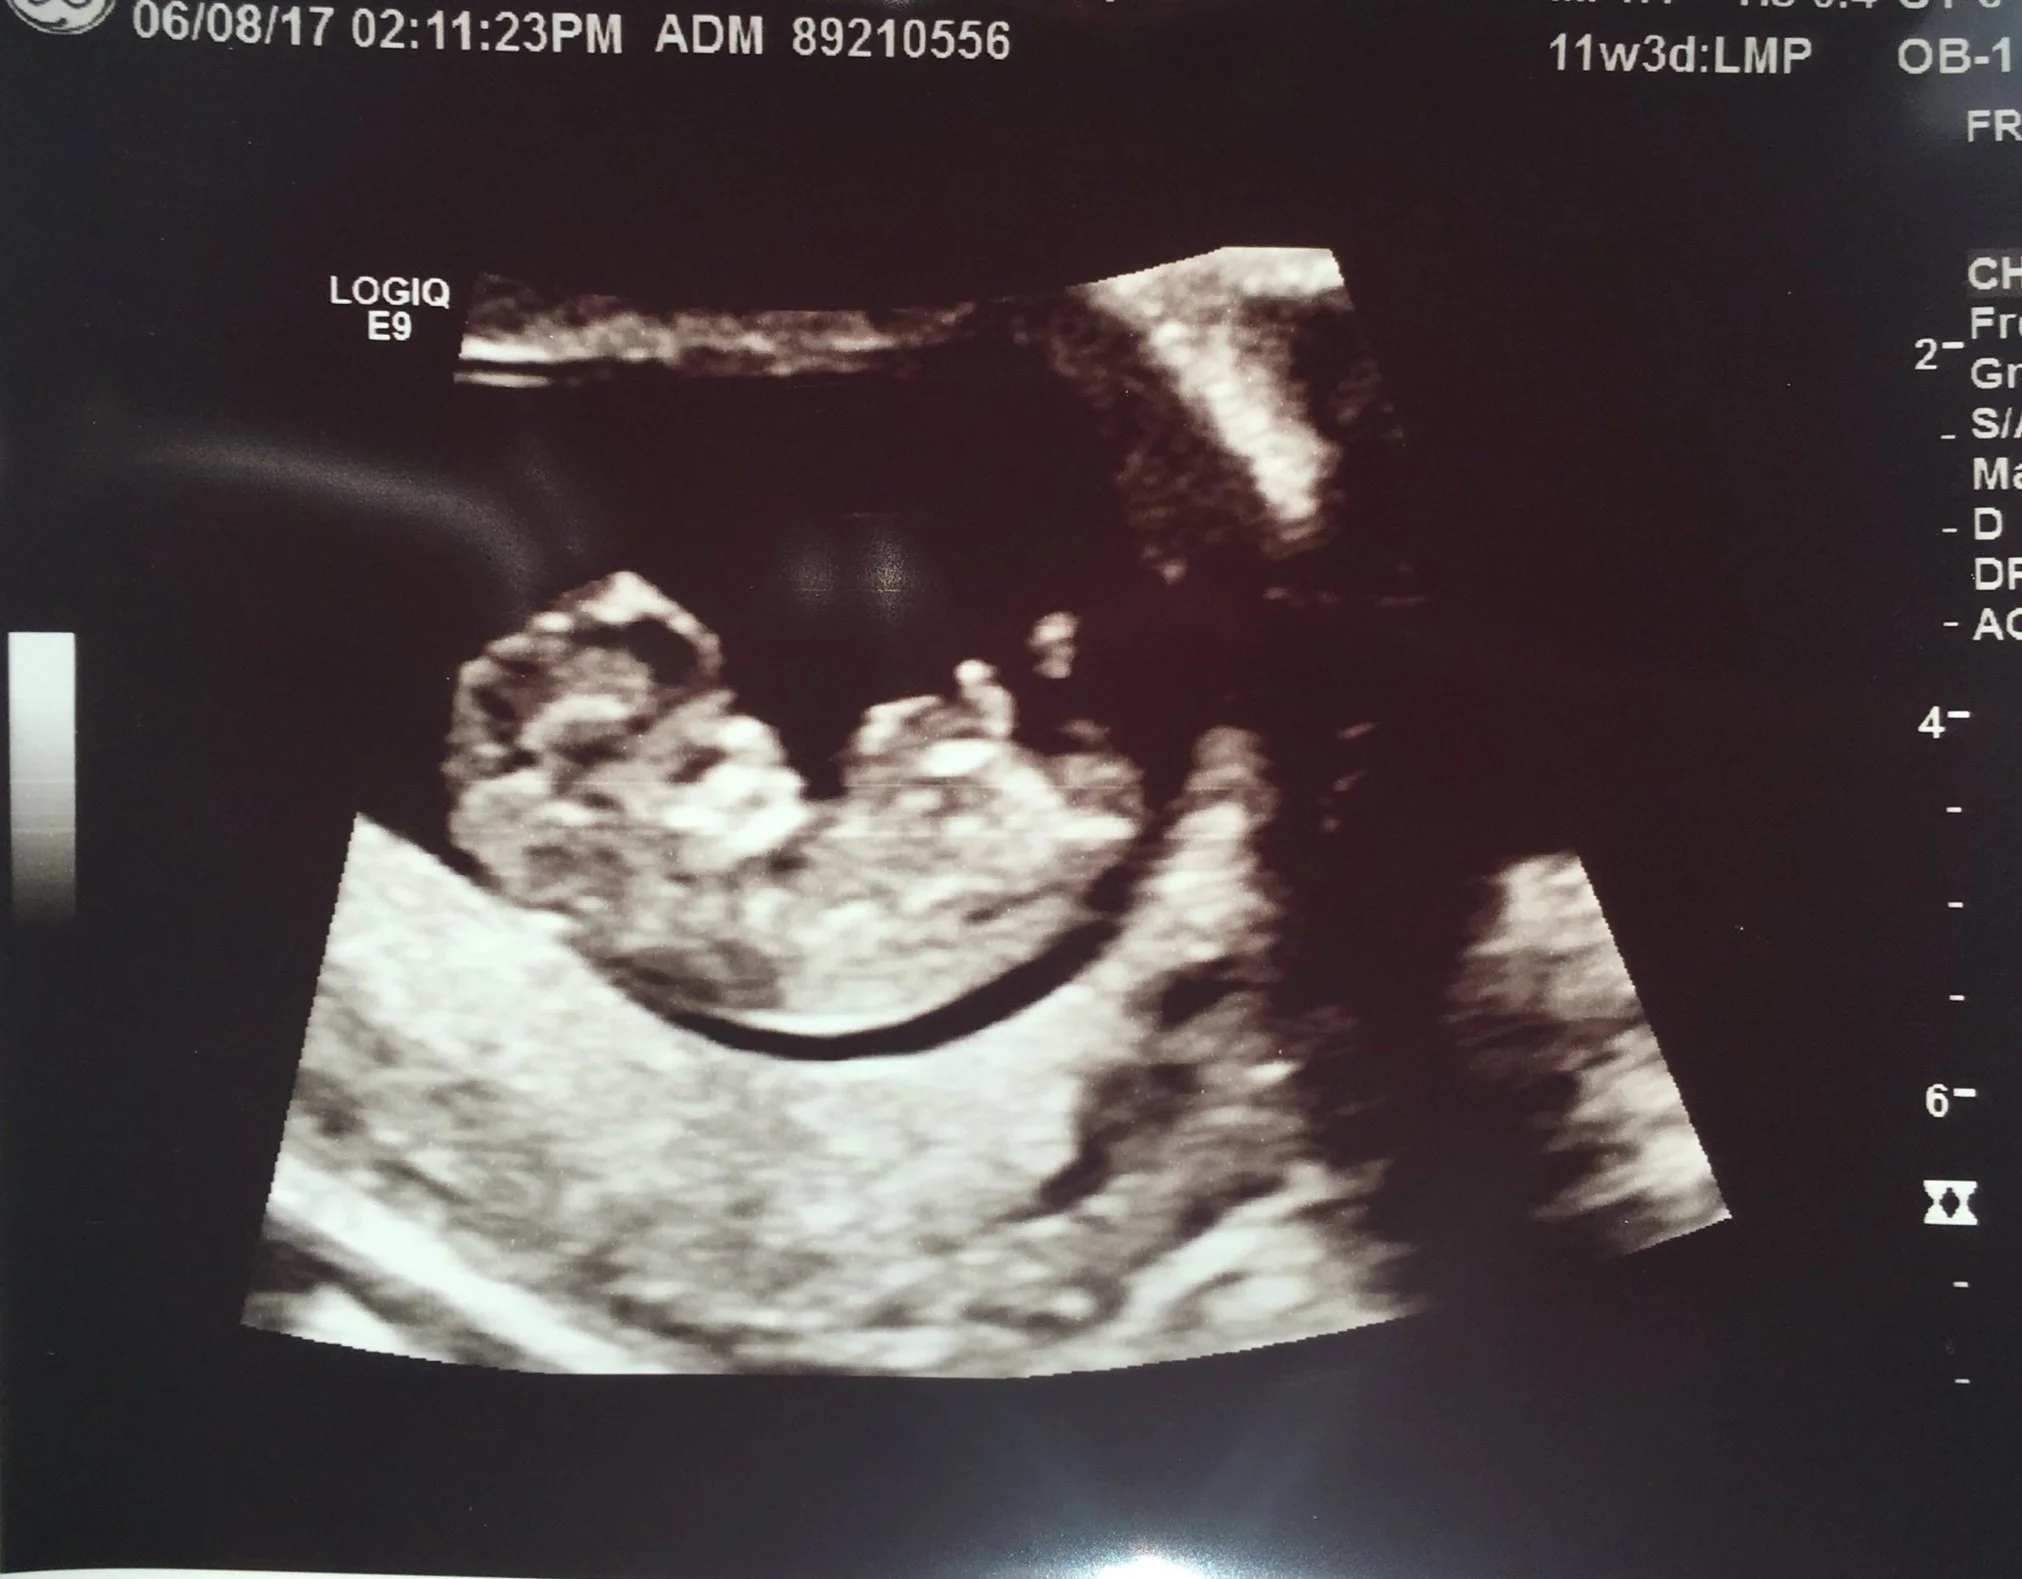

Just over 11 weeks, I was still so sick, but seeing her grow muted all the symptoms I had.